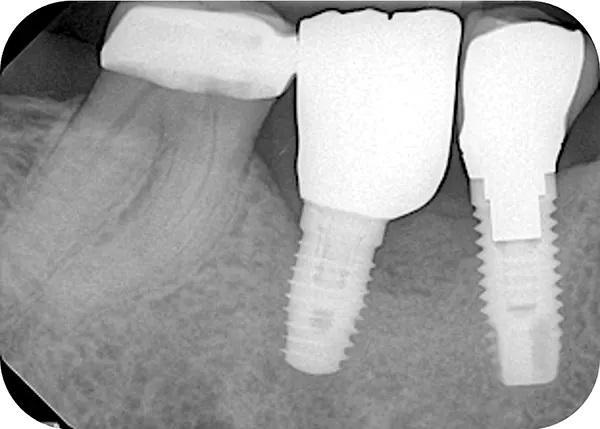

Пациент приходил для осмотра через 1, 2, 4, 6 (снятие швов), 8, 12, 16 и 24 недели (фото 10). Пациент четко соблюдал рекомендации, поэтому отлично контролировал образование зубного налета. Положенные раз в полгода процедуры по профилактике были проведены в срок 14 недель после проведенного вмешательства. Клиническое обследование через 24 недели выявило увеличение объема как горизонтального, так и вертикального альвеолярного отростка (фото 11) по сравнению с исходным уровнем (фото 3 –фото 5).

Фото 10. Периапикальная рентгенограмма через 24 недели после НКР с фиксирующими винтами и добавлением гранул остеопластического материала в добавление к использованию коллагеновой мембраны. Можно наблюдать умеренную резорбцию большей части корональных частиц.

Стандартные рентгенограммы были сделаны сразу после операции и через 8 и 24 недели (фото 10). Вторая КЛКТ была сделана через 24 недели (фото 12). После интерпретации снимка было подтверждено, что благодаря процедуре направленной регенерации костной ткани удалось восполнить достойный обьем костной ткани в вертикальной и горизонтальной плоскости для последующей установки дентального имплантата (фото 6 и фото 12).